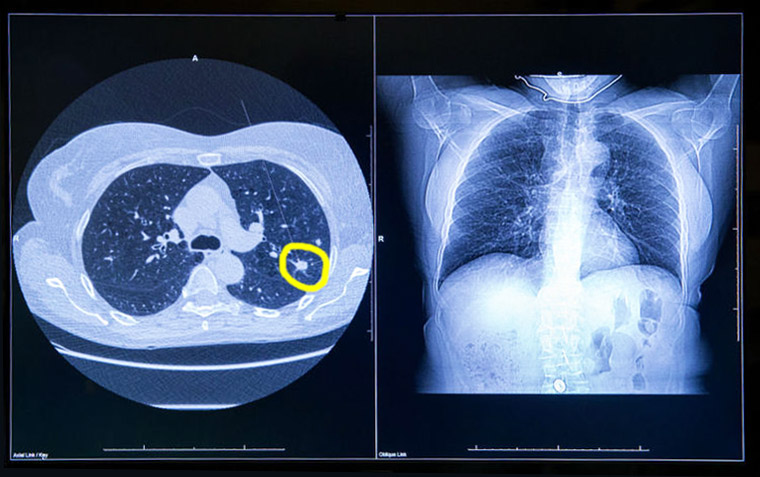

Seguimiento diagnóstico de los resultados positivos en la tomografía computada de baja dosis en rastreo de cáncer de pulmón

Del total de participantes, el 12,4% recibió un diagnóstico de cáncer de pulmón en el plazo de un año. Se realizaron procedimientos invasivos al 16,2% de todos los participantes y al 7,3% de aquellos sin cáncer de pulmón eventual. Alrededor del 60% de los participantes recibió atención acorde con las directrices, y aproximadamente un tercio recibió cuidados menos intensivos. Las tasas de procedimientos invasivos en aquellos sin cáncer fueron bajas. Annals of Internal Medicine, diciembre de 2025.

Importancia pronóstica de la determinación del calcio coronario en la TC de tórax para el rastreo de cáncer de pulmón

En las personas que se sometieron a una TC de tórax de baja dosis para la detección del cáncer de pulmón, la presencia de calcio en la arteria coronaria fue un predictor independiente de muerte por cualquier causa y eventos cardiovasculares, incluso después del ajuste por muerte no cardiovascular. Canadian Medical Association Journal, 2 de diciembre de 2024.

Detección del cáncer de pulmón mediante TAC de baja dosis en Francia: resultados finales del estudio DEP KP80

Este estudio demostró la viabilidad y eficacia del cribado del cáncer de pulmón en un contexto de la vida real, en el que la mayoría de los cánceres de pulmón se diagnostican en una etapa temprana y se extirpan quirúrgicamente. Nuestros resultados también destacaron la importancia de la participación en cada ronda, subrayando el hecho de que optimizar la organización es un objetivo principal. eBioMedicine, noviembre de 2024.

El desarrollo y desempeño de criterios alternativos para la detección del cáncer de pulmón

Estos resultados sugieren que criterios alternativos y simples para el rastreo de cáncer pulmonar pueden identificar sustancialmente más personas con altos beneficios, especialmente en algunos grupos raciales y étnicos. Annals of Internal Medicine, 20 de agosto de 2024.

Impacto de una ronda única de detección de cáncer de pulmón por TC de baja dosis sobre la causa de mortalidad en diferentes grupos socioeconómicos

Los dos quintiles inferiores de nivel socioeconómico se beneficiaron de una única ronda de detección con tomografía computada de dosis baja en términos de supervivencia al cáncer de pulmón (HR 1,89, IC 95 % 1,16–3,08) en la misma medida que los quintiles superiores (HR 1,87, IC 95 % 1,07–3,26). Sin embargo, hubo un mayor impacto en las muertes por EPOC y enfisema en los quintiles más desfavorecidos. The Lancet Regional Health Europe, 21 de mayo de 2024.